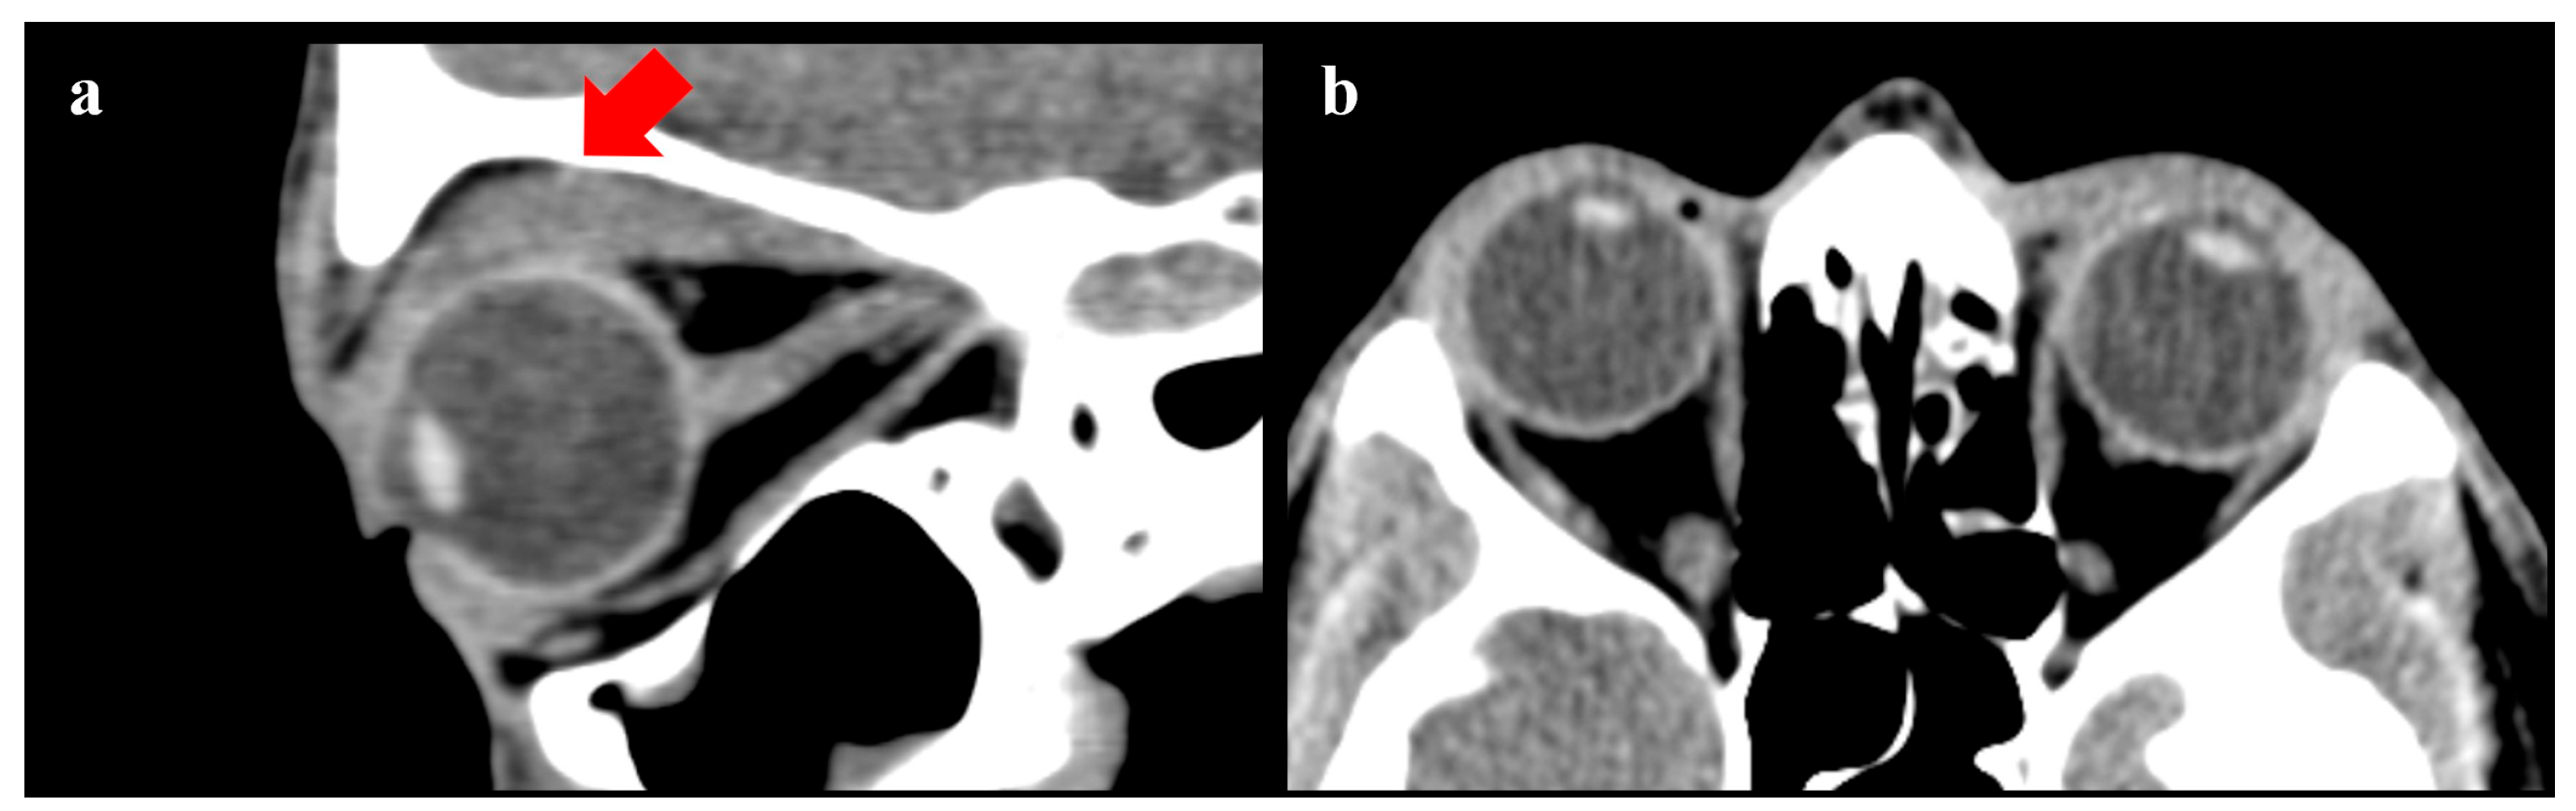

| Joseph A. et al. (2018) [24] | Book chapter | “…Eyelid retraction, lid lag on downgaze and lagophthalmos, and decreased convergence may be found in patients with thyroid-related orbitopathy. Blepharoplasty should be reserved for patients with quiescent disease and undertaken after any proptosis, motility dysfunction, and eyelid retraction have stabilized for 6 months to 1 year or have been definitively treated. In patients with suspected thyroid eye disease, referral to an endocrinologist or internist may be necessary for appropriate systemic workup, including serum thyroid hormone levels (triiodothyronine [T3], levorotatory thyroxine [T4], thyroid stimulating hormone [TSH]). Orbital computed tomography may demonstrate enlargement of the extraocular muscles and increased orbital fat when systemic signs are completely lacking early in the course of the disease…” |

| Kwitko G.M. et al. (2021) [28] | Review | “...Most contraindications for ptosis surgery revolve around the exposure of the cornea. Conditions like thyroid orbitopathy, progressive external ophthalmoplegia, or loss of Bell’s phenomenon can make patients more prone to exposure keratopathy after ptosis surgery: a more conservative approach is needed in these patients…CT scan of the orbits should be obtained if an orbital process such as thyroid orbitopathy or an orbital tumor is suspected. Slit lamp evaluation is essential to detect corneal erosions or dry eye…” |